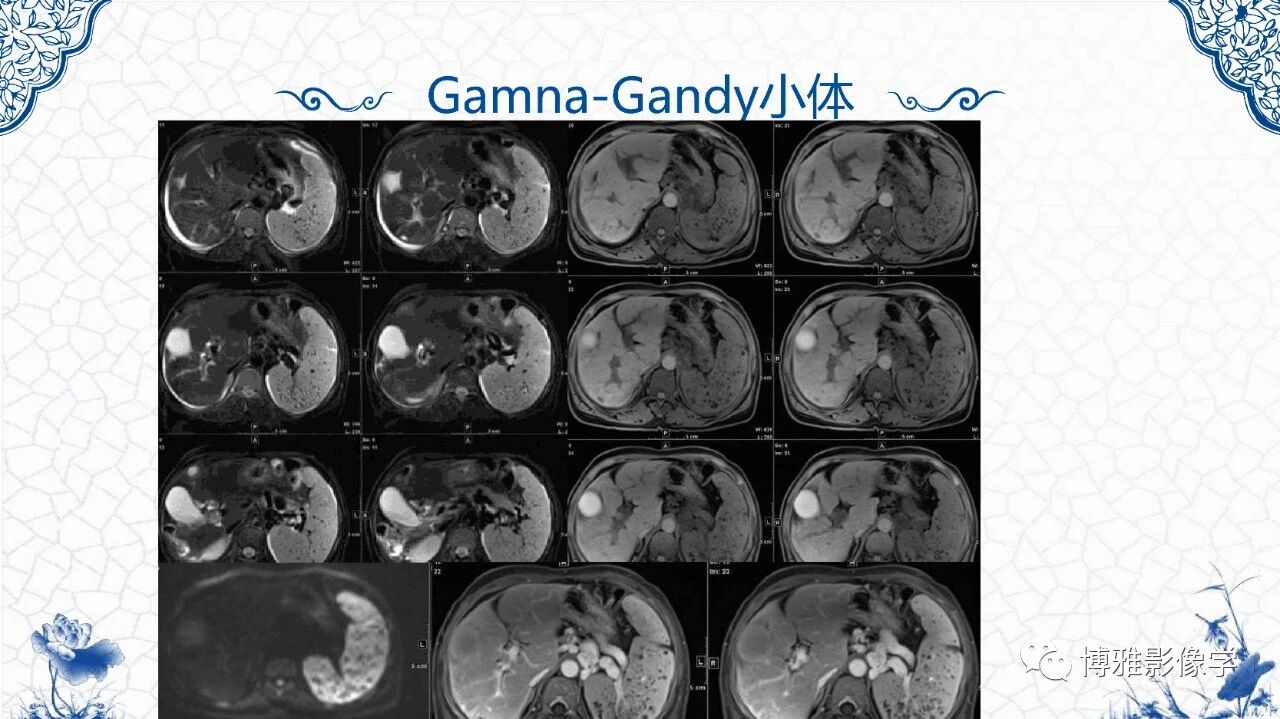

脾脏非肿瘤影像诊断